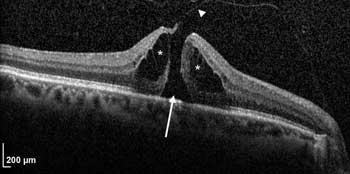

Photonics Reveals Dangers Lurking in Water Sources

Fluorescence detection and surface plasmon resonance spectroscopy could help make water safer. “Water, water, every where, nor any drop to drink,” wrote Samuel Taylor Coleridge more than two centuries ago. And nowadays, there is far less...